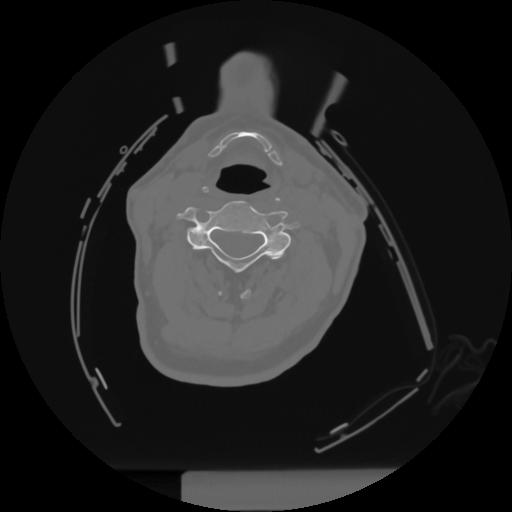

12 P.BLANDAS,,Vol,0.5,P.BLANDAS,,